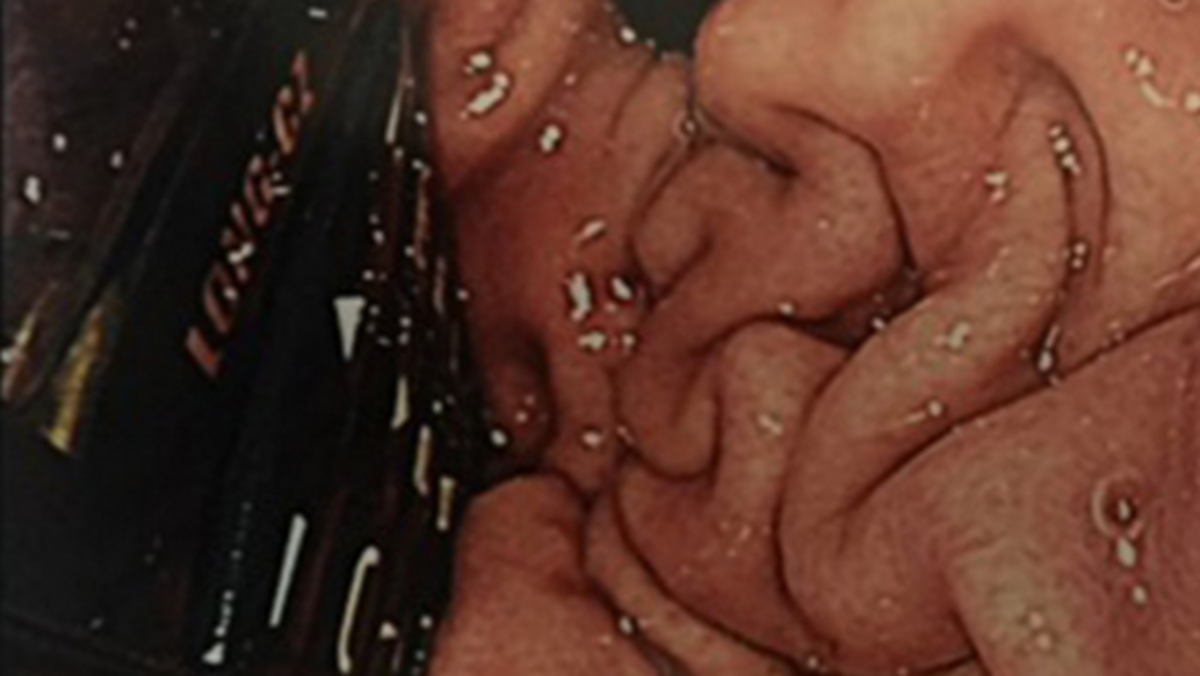

وحاول المسعفون في بداية الأمر إخراج الهاتف عبر إدخال منظار طبي إلى جوف السجين، لكن هذه المحاولة أخفقت.

وأشاروا إلى أن الأمر يتطلب إجراء عملية شق البطن وإخراج الهاتف الذي استقر في المعدة، واستطاعوا في نهاية المطاف إخراج الهاتف من خلالها.

وأظهرت الأشعة السينية ان الهاتف المحمول الذي ابتلعه السجين والبالغ من العمر 29 عاما سليم ولم يتأثر بالحامض المعدي.